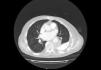

Presentamos el caso de un varón de 75 años que consultó por síndrome constitucional con pérdida ponderal de unos 10kg en 3 meses, acompañado de dolor de perfil pleurítico en hemitórax izquierdo y disnea intermitente. Como dato adicional comentó un traumatismo perforante en dicho hemitórax acontecido en años previos. Como antecedentes personales, el paciente carecía de hábitos tóxicos; sin exposición a agentes físicos ni químicos; hipertensión arterial, diabetes mellitus tipo 2, cardiopatía isquémica y fibrilación auricular permanente anticoagulada. A la exploración lo único que destacó fue un estado caquéctico con hipoventilación en ambas bases pulmonares y saturaciones basales de oxígeno del 98%. En la radiografía de tórax se observó un ascenso del hemidiafragma izquierdo asociado a un área basal de consolidación pulmonar y un extenso engrosamiento pleural, compatible con paquipleuritis. En la analítica se constató anemia normocítica compatible con trastornos crónicos, neutrofilia sin leucocitosis, beta-2 microglobulina discretamente elevada e hipoalbuminemia sin presencia de picos clonales. En la tomografía computarizada (TC) de tórax se visualizó una tumoración de unos 5,3×9,6cm, adyacente a la aorta torácica descendente, captante con la administración de contraste, que parece contactar con bronquio lobar inferior izquierdo y anexa a área extensa de calcificación pleural, sin objetivarse adenopatías asociadas (fig. 1). El resto del estudio de extensión fue normal. Se realizó tomografía por emisión de positrones/tomografía computarizada (PET/TC) para intentar filiar la naturaleza de la lesión y completar el estudio, observándose un aumento de la actividad metabólica de la lesión descrita, con una elevada tasa de proliferación celular y posible infiltración de la vértebra D9, así como en región posterolateral de la pared torácica. El paciente fue desestimado para la realización de fibrobroncoscopia por inaccesibilidad de la lesión a través de dicha técnica. Se realizó biopsia con aguja gruesa (BAG) guiada por tomografía de la lesión, con resultado histológico de linfoma difuso de células grandes B NOS, virus de Epstein-Barr (EBV) positivo. El paciente fue remitido a consultas de oncología médica para planificación del tratamiento y seguimiento.

Los linfomas pulmonares primarios son muy raros, constituyendo menos del 1% de los casos de neoplasias pulmonares; entendiendo estos como la afectación exclusiva del pulmón, sin evidencia de afectación extratorácica, tumor mediastínico, de ganglios linfáticos o médula ósea4. Suelen presentarse con más frecuencia con afectación bilateral y en forma de tumoraciones o nódulos que suelen cavitarse en un 50% de los casos. Menos frecuentemente se manifiestan como área de vidrio deslustrado, afectación pleural, broncograma aéreo, imagen reticular o atelectasia lobar3. El linfoma difuso de células grandes B (DLBCL) supone la forma más común de linfomas no Hodgkin (LNH) constituyendo entre un 15-25% de los casos según las series1,4. Este tipo de linfomas está formado por un grupo heterogéneo con entidad clínica, morfológica, genética y biológica propia. La localización extranodal más frecuente es el tracto gastrointestinal. Suele diagnosticarse con más frecuencia en varones por encima de los 60 años, aunque se han reportado casos en pacientes menores de 30 años. La mitad de estos tumores son diagnosticados en fase diseminada y la otra mitad como enfermedad localizada, entendida como aquella área que puede estar contenida en un campo de irradiación. El DLBCL es localmente muy invasivo. El DLBCL positivo al EBV es una variante específica, añadida en la revisión de 2016 de la Organización Mundial de la Salud. Puede manifestarse en cualquier edad y se suele dar en pacientes sin inmunodeficiencia previa ni otros linfomas1. Esta entidad puede solaparse con la granulomatosis linfomatoide, que difiere en la aparición de células B EBV positiva (siendo escasas en la última referida). En nuestro caso la peculiaridad que introducimos es la manifestación muy poco frecuente de estos tumores como linfoma pulmonar primario, como área de consolidación pulmonar unilateral y no cavitada. No hemos podido establecer ninguna relación con el área de calcificación pleural crónica residual tras la revisión de una extensa bibliografía.